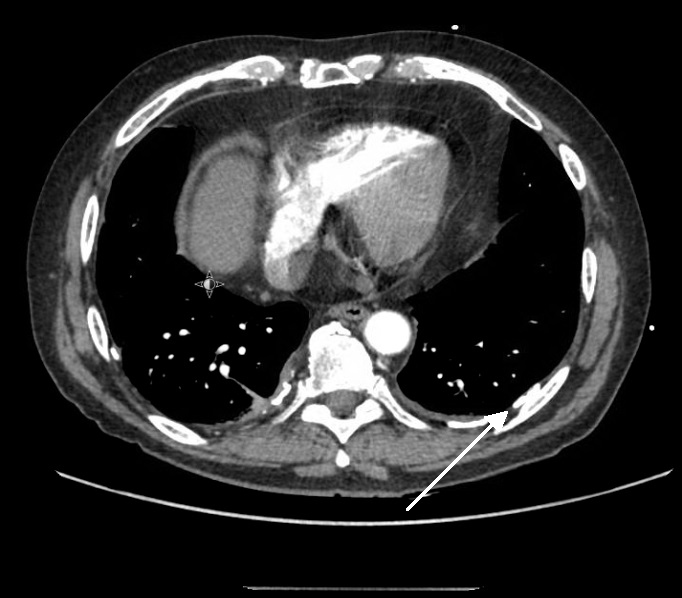

4 Pleural plaques. CT chest (axial view) showing multiple, bilateral Do Pleural Plaques Grow Pleural plaques are caused by exposure to asbestos at some time in the past. Pleural plaques are deposits of hyalinized collagen fibers in the parietal pleura. Pleural plaques are benign areas of thickened tissue in the lung lining's outer layer or parietal pleura that can develop 10 to 30 years. Pleural plaques are areas of tissue that become thickened in. Do Pleural Plaques Grow.